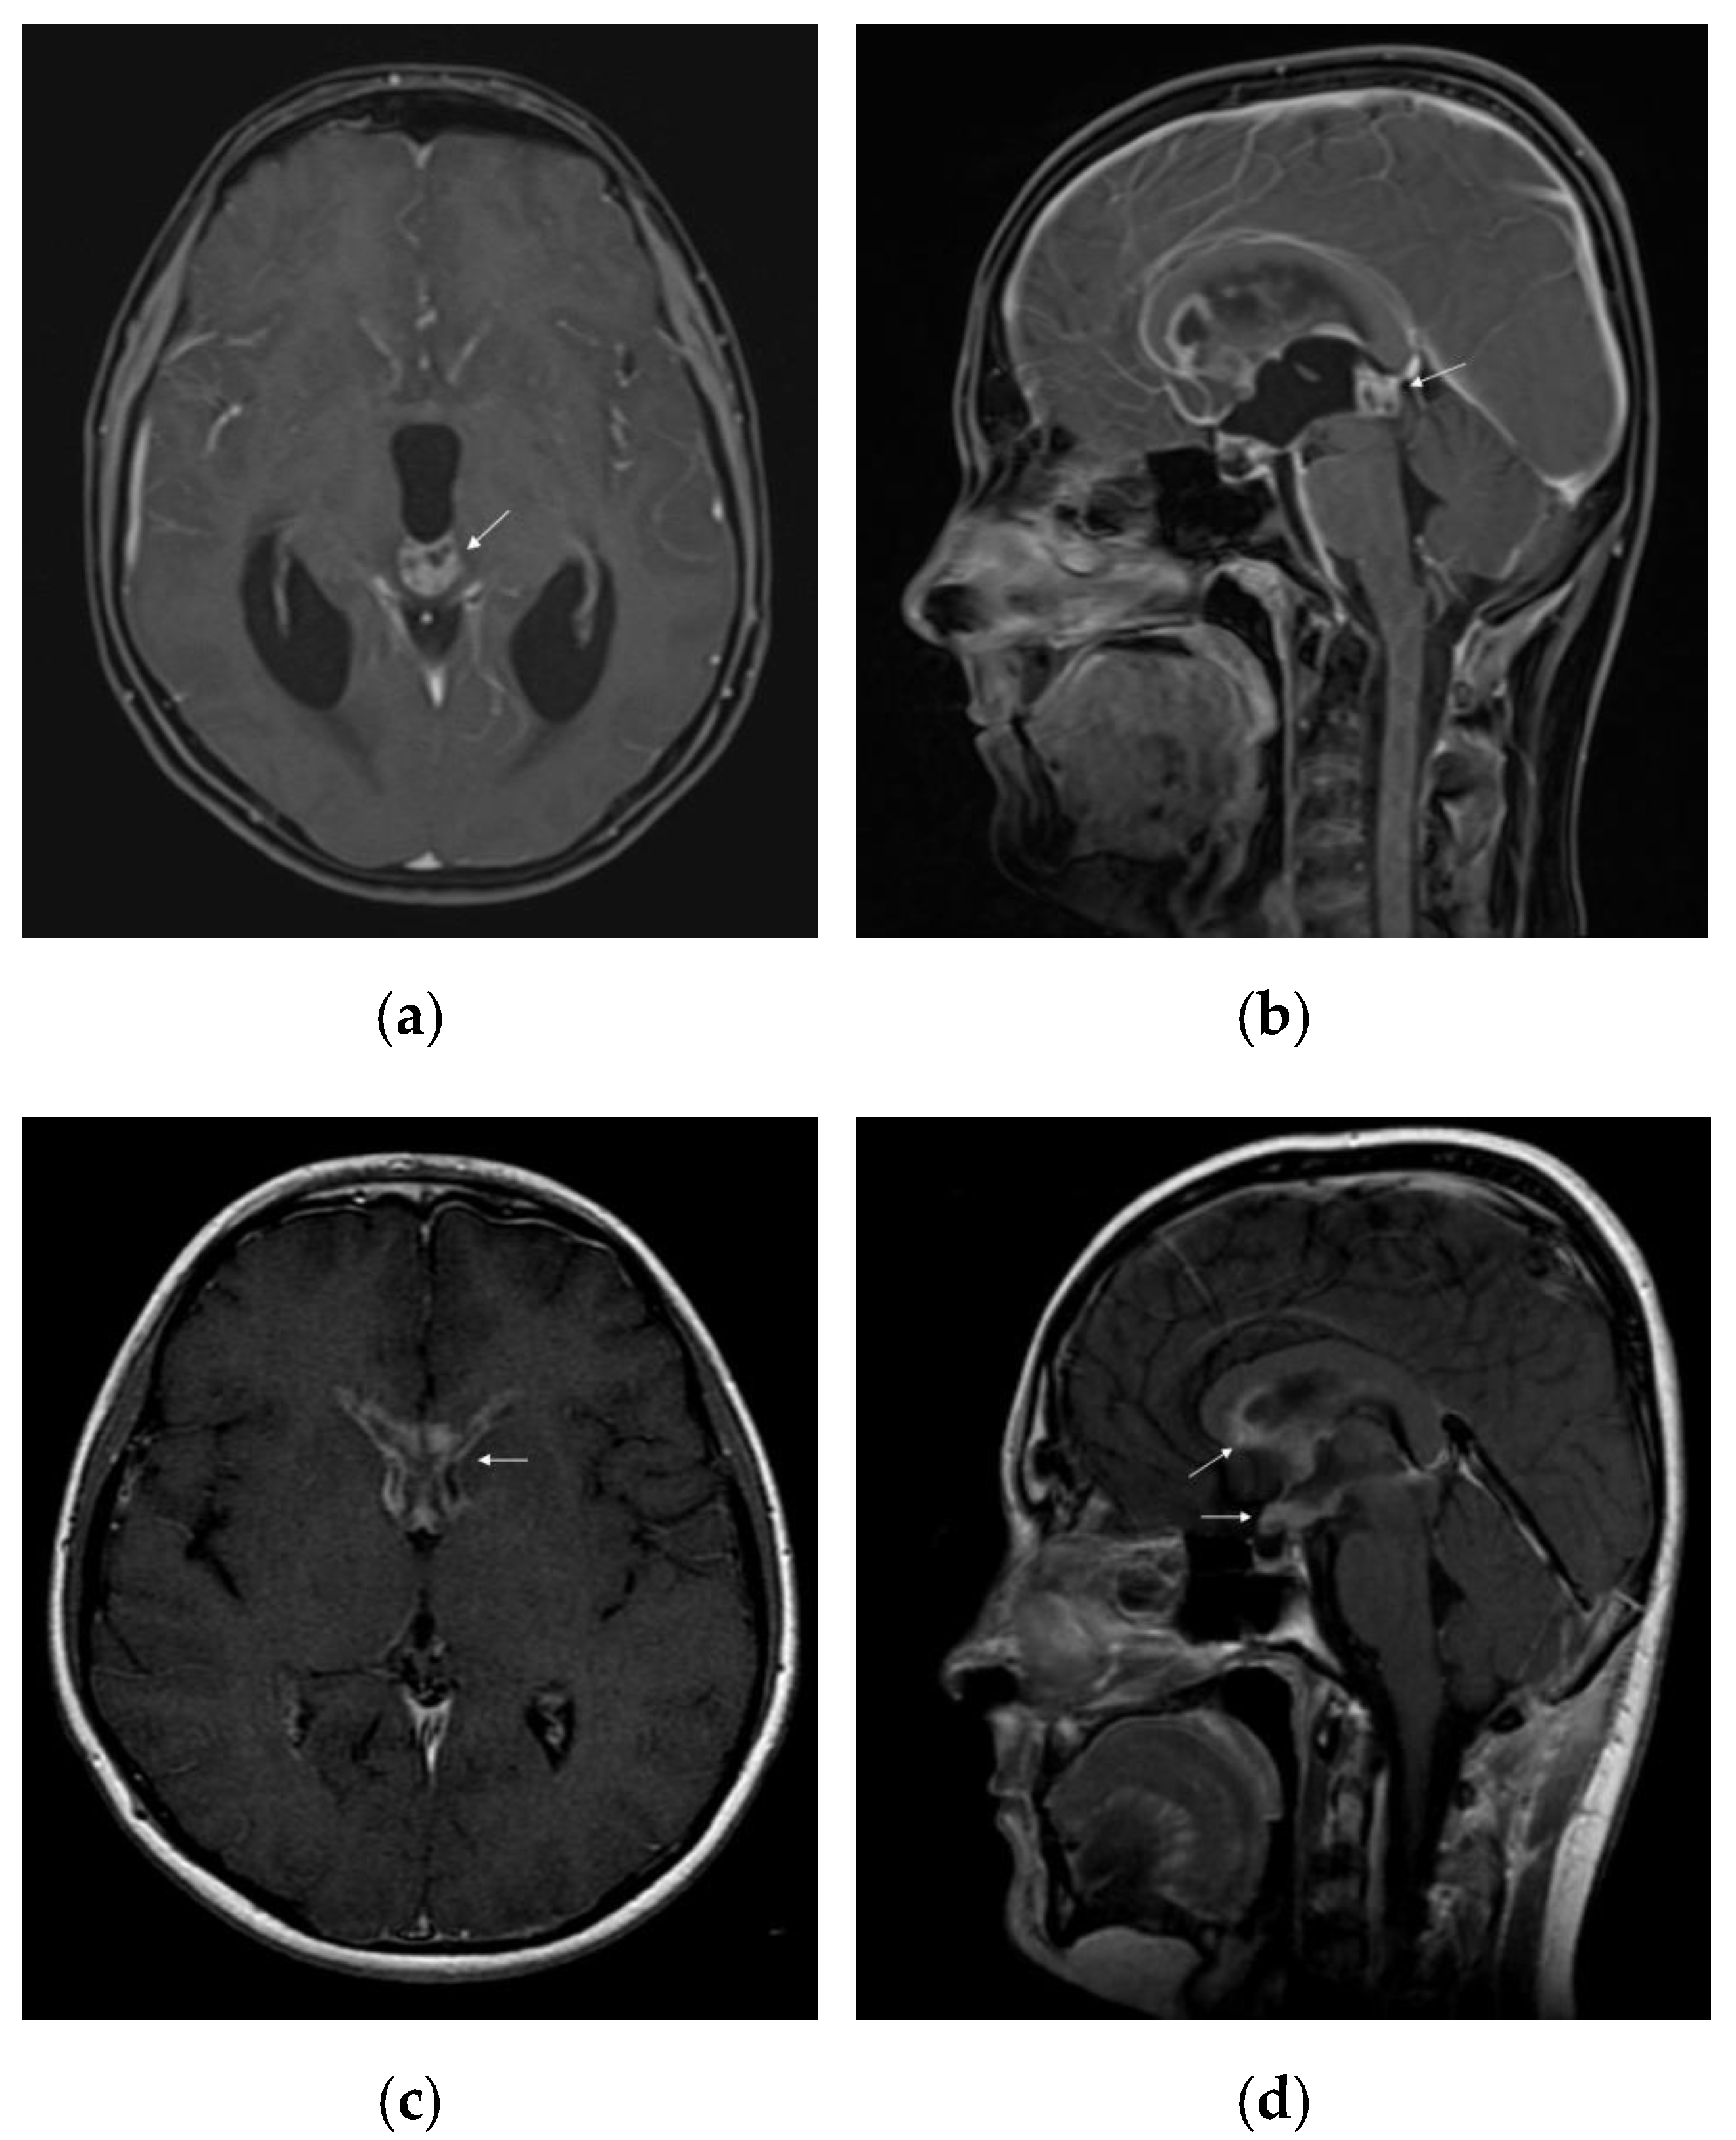

On standard MRI, germinomas appear as heterogeneous tumours in T1/T2-weighted imaging, in 40% of the cases, and the uptake of the gadolinium can be either homogeneous (47%) or heterogeneous (53%) []. Relevant images of a pure pineal germinoma are shown in Figure 2.

Figure 2.

MRI features of intracranial germinoma in a teenage patient: (a) pineal germinoma: heterogeneous contrast enhancement on axial gadolinium-enhanced T1-weighted image, with a tendency to cardioid shape; (b) pineal germinoma: heterogeneous contrast enhancement on sagittal gadolinium-enhanced T1-weighted image; (c) postoperative disseminated disease: bilateral nodular enhancement of anterior horns of the lateral ventricles on axial gadolinium-enhanced T1-weighted image; (d) postoperative disseminated disease: nodular enhancement of the hypothalamus, optic chiasm, mammillary bodies, and corpus callosum on sagittal gadolinium-enhanced T1-weighted image.

Multiple imaging studies have been conducted to provide a better characterization of germinomas. For example, Inoue et al. showed that 90% of the patients with pineal germinomas presented a cardioid-shape tumour image on the axial MRI views, due to its progression pattern on both sides of the third ventricle, concluding that this was a specific aspect for pure pineal germinoma []. Awa et al. described two significant features differentiating pineal germinomas from NGGCT: peritumoural edema thicker than 5 mm (peritumoural area with T2 hyperintensity) and bithalamic extension []. T2* (T2-star) sequence is generally used to obtain a better characterization of intratumoural/intraventricular/cerebral microhaemorrhage, iron deposits, and calcifications []. Susceptibility-weighted imaging (SWI) or T2* gradient echo (GRE) technique can be used for better differentiation between pure germinoma and NGGCT in the pineal region: 93% of the germinomas present iso- or hyperintensity, whereas NGGCT are hypointense compared to the healthy brain []. Another imaging technique, such as the arterial spin labelling based perfusion-weighted MRI (ASL-PWI) could be used in differentiating germinomas from NGGCT, based on lower values of relative tumour blood flow encountered in germinomas []. Calcification can be present in both germinomatous and non-germinomatous pineal tumours [].